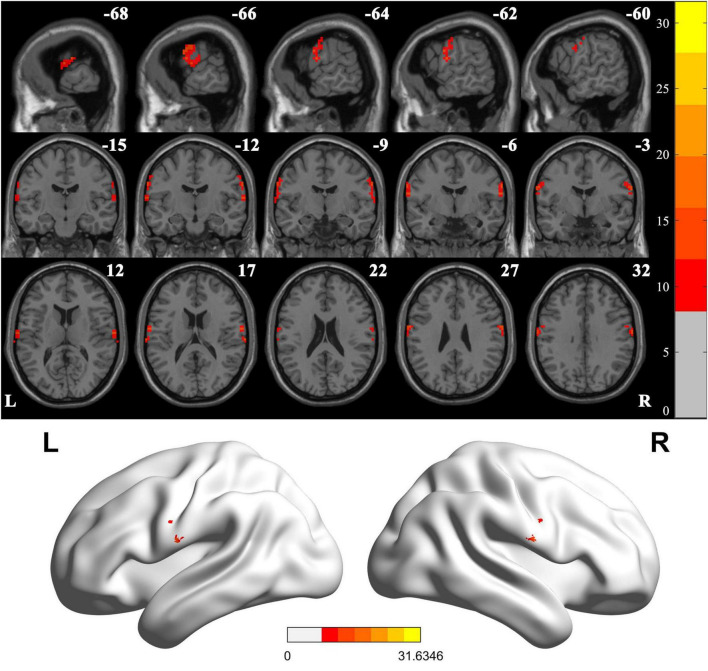

Results: The results indicated that compared to the HC group, significant differences were detected in postcentral gyrus, extending to precentral gyrus in both BGIS groups. Post hoc analysis showed that in the pairwise ROI-based comparison, individuals with LBGIS and RBGIS exhibited reduced VMHC values compared to HC groups. There was no significant difference between the LBGIS and RBGIS groups. In the LBGIS group, the VMHC value showed a negative correlation with NIHSS and a positive correlation with BI.

Conclusion: The analysis of VMHC in rs-fMRI revealed a pattern of brain functional remodeling in patients with unilateral BGIS, marked by reduced synchronization and coordination between hemispheres. This may contribute to the understanding of the neurological mechanisms underlying motor dysfunction in these patients.